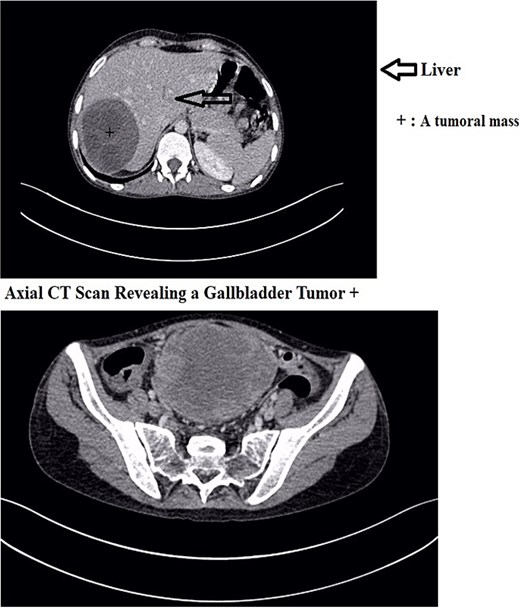

A 30-year-old woman, gravida 2 para 2, presented with a 10-day history of right upper quadrant (RUQ) abdominal pain. She had no significant medical or surgical history and denied systemic symptoms such as fever, weight loss, or fatigue. On examination, she was afebrile and hemodynamically stable, with a WHO performance status of 1. Abdominal palpation revealed localized tenderness in the RUQ. Laboratory investigations revealed mild leukocytosis (12 250/μL), Hb:10.8 g/dL, Plt:538000, TP:64%, Na:132 mmol/L, K:4.1 mmol/L, CRP:299 mg/L. Liver function tests showed GGT:36 U/L, PAL:46 U/L, ASAT:13 U/L, ALAT:6 U/L, total bilirubin:5 mg/L, direct bilirubin:3 mg/L. Urea and creatinine were 0.2 and 3.6, respectively. Contrast-enhanced CT revealed a large mass in the gallbladder bed, suspected to be a tubulo-papillary intracholecystic neoplasm (ICPN) (Figs 1 and 2), with an associated angiomatous liver lesion in segment III, hydatid cysts, and mild ascites. Exploratory laparotomy was performed, revealing a ruptured gallbladder tumor with extension into adjacent liver tissue and abdominal wall, and free biliary stones within the peritoneal cavity (Fig. 3).

A coronal CT scan of the abdomen showing a large, well-defined hypodense mass in the right hepatic lobe.